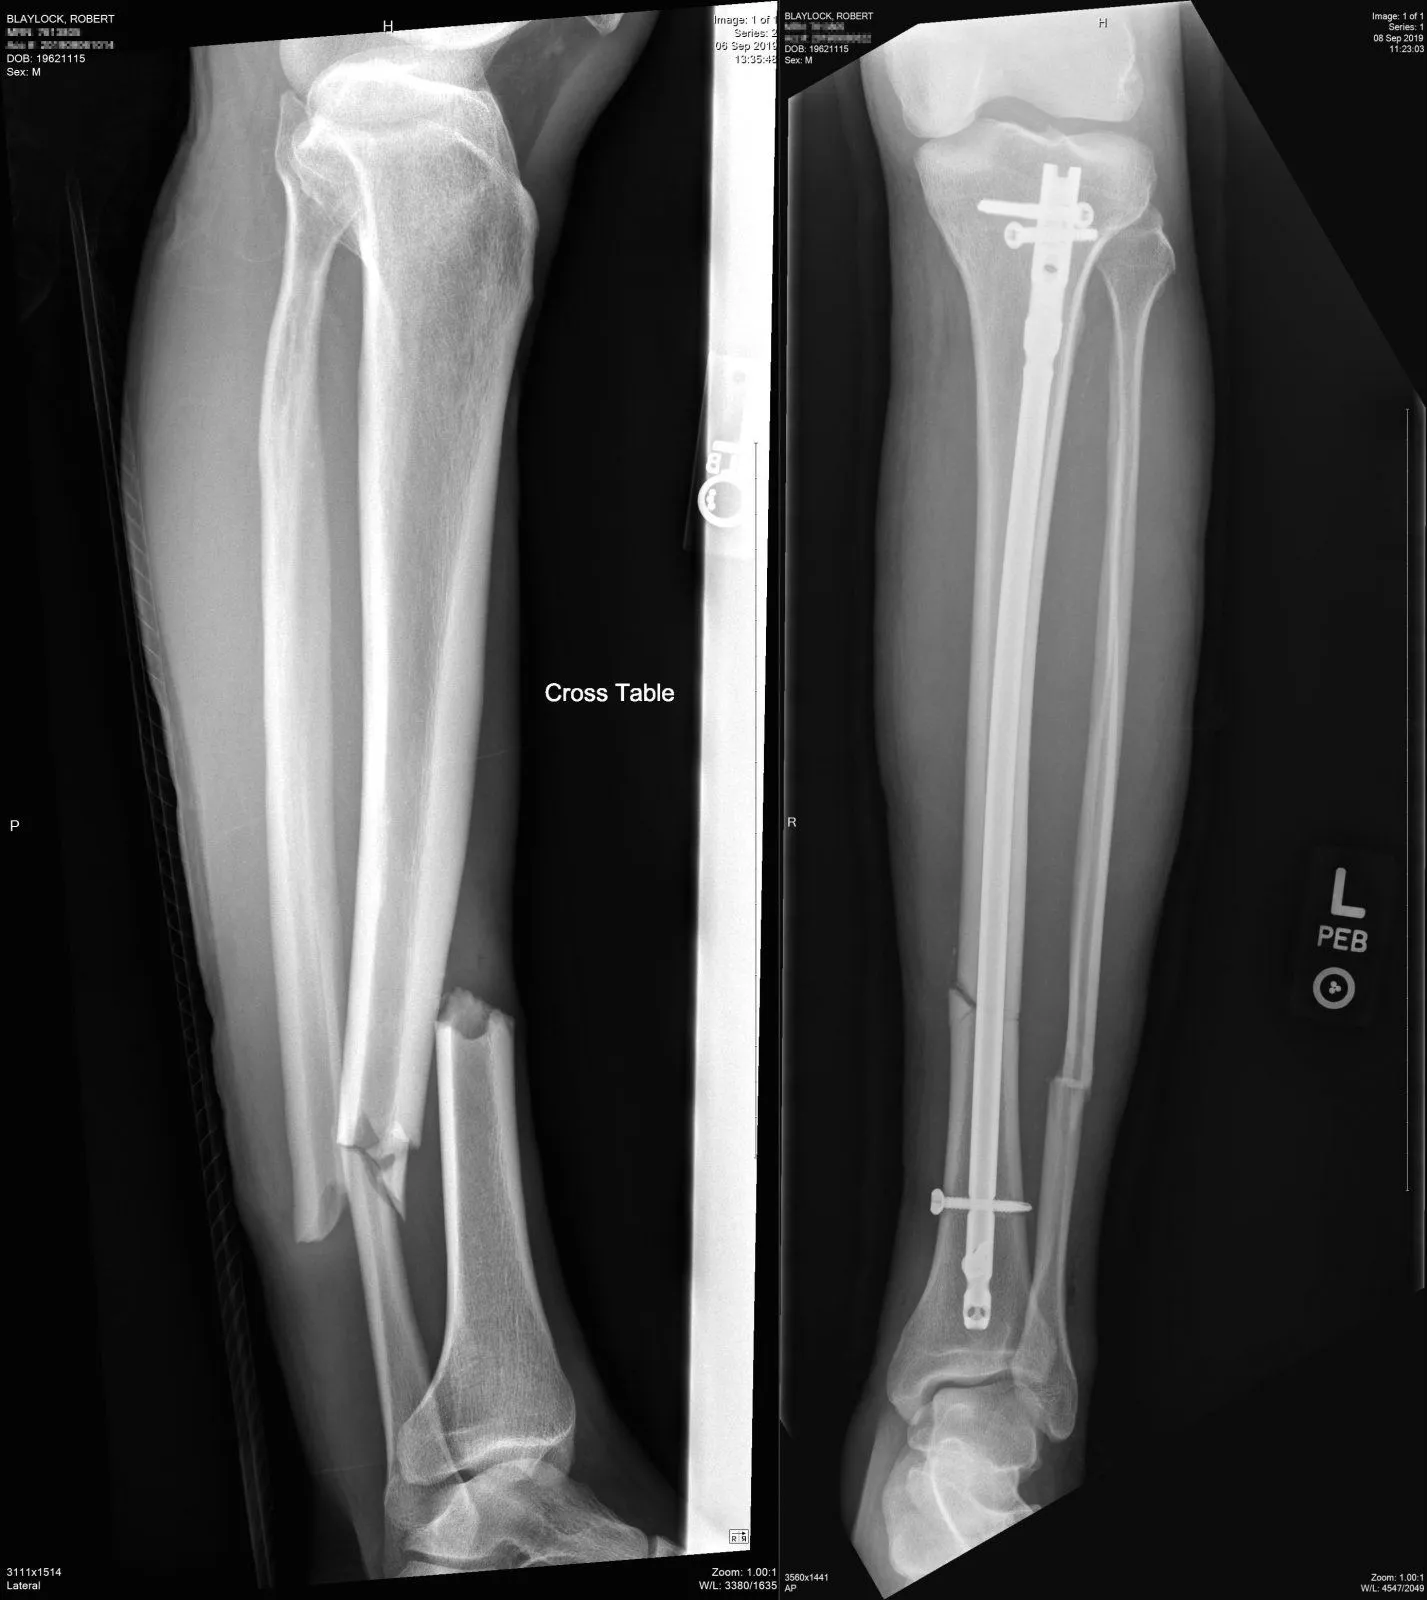

At some time during my recovery from my broken leg, my nurse/case manager brought up the subject of a bone stimulator. Both my orthopedic surgeon and my occupational doctor expressed great skepticism about such devices, and recommended against it.

During these conversations, I mentioned the claim about a cat's purring, and wondered if these bone stimulators worked on a related principle. I also faintly toyed with the idea of constructing a device that I could strap to my leg, that would vibrate at the approximate frequency of a cat purring.